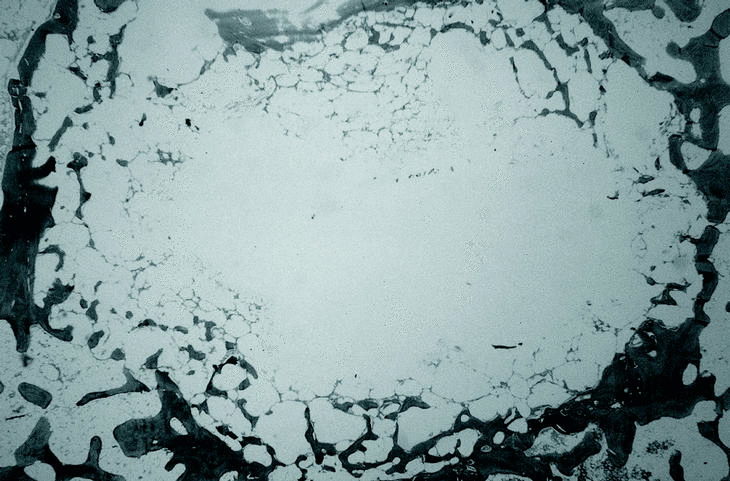

En el grupo PLA 50/50 (30.000) (fig. 4) se observó la formación de trabéculas óseas que invadían el implante de forma centrípeta. En estas trabéculas se apreció una gran actividad osteoblástica, con abundantes frentes de osteoblastos que en algunos casos llegó a ocupar la totalidad del defecto óseo creado a las 12 semanas. Se apreciaron células gigantes multinucleadas. Se observaron restos de polímero pero en menor cantidad que en los tres grupos previos.

Figura 4. Grupo PLA 50/50 30.000 a las 12 semanas. Abundante neoformación ósea trabecular centrípeta (Tric.,x10).